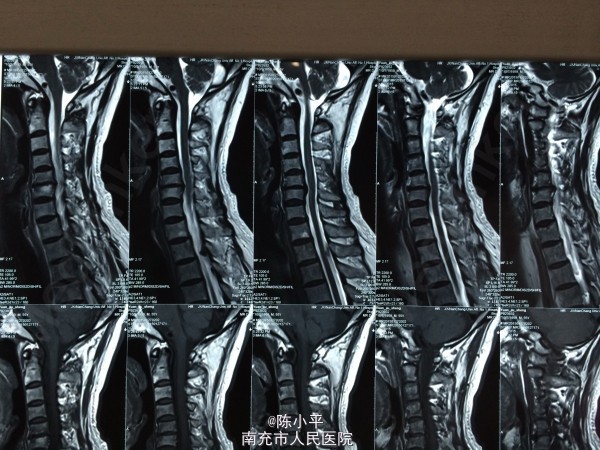

患者男性,56岁,自述肩部无力半年多,会诊后诊断为肌萎缩型颈椎病(颈4.5椎体不稳、颈5/6椎间盘突出),查体:左上肢肌力正常,左拇指麻木,右上肢肱三头肌、右手握力约4级,小指麻木,虎口区肌肉萎缩,双下肢肌力、感觉正常。双手霍夫曼征阴性。